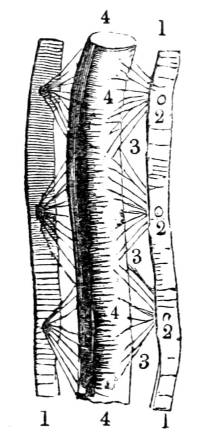

View of the trachea, showing, first, the division of the

tube into the right and left bronchus, and the subdivision

of the bronchi into the bronchial tubes; and secondly, the

membranous and cartilaginous tissues of which the organ

is composed.